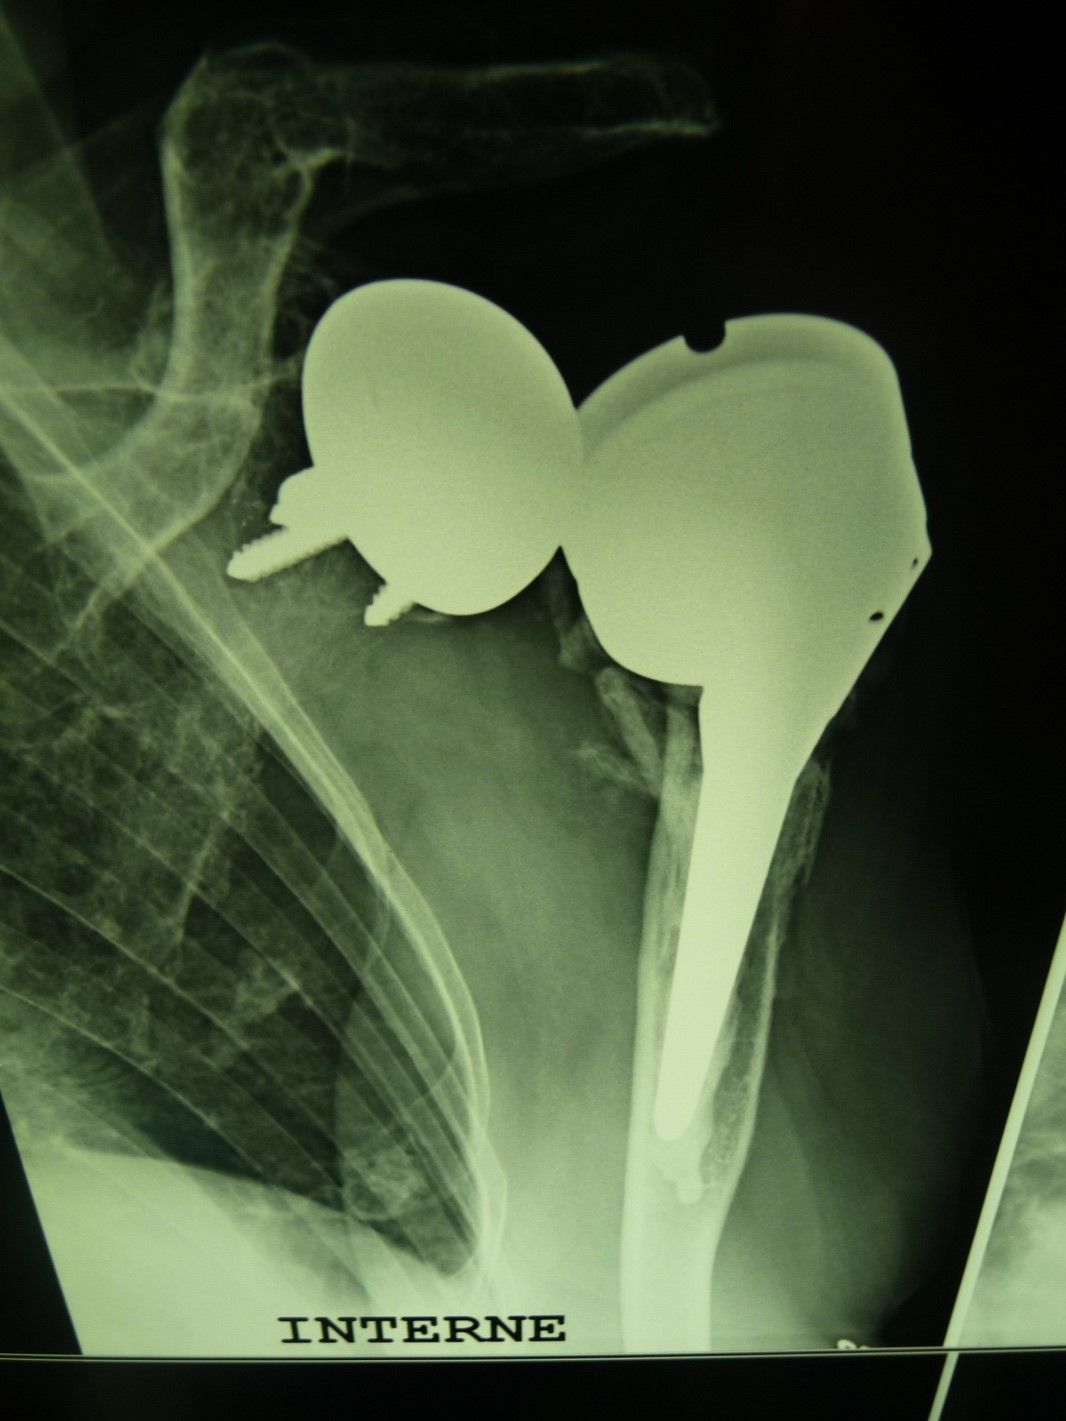

Webinaire Cours Supérieur de l'Épaule 2023 - La prothèse d'épaule , Pierre Métais Hôpital privé la Châtaigneraie, Beaumont, France , Geoffroy Nourissat Hôpital Saint-Antoine, 75012 Paris, France 🖂 gnourissat@wanadoo.fr , Jean Kany Clinique de l’Union, Saint-Jean, France , Jean-David Werthel Hôpital Ambroise Paré, Paris, France , Bruno Zipoli Centre Hospitalier Dax - Côte d'Argent, Dax, France avril 2023

Mise au point Comment prendre en charge une arthroplastie totale inversée instable de l’épaule ? : Étude rétrospective de 25 cas , Philippe Valenti Institut de la main - Clinique Jouvenet, Paris, France , Jean Kany Clinique de l’Union, Saint-Jean, France , D. Katz Clinique du Ter, 56270 Ploemeur - , Jean-David Werthel Hôpital Ambroise Paré, Paris, France N°292 - Mars 2020 ● 14 min de lecture

Mise au point Plaidoyer en faveur du concept d'embase glénoïdienne métallique dans les prothèses totales anatomiques d'épaule , D. Katz Clinique du Ter, 56270 Ploemeur - , P. Sauzières Clinique Jouvenet, 75016 Paris - , Philippe Valenti Institut de la main - Clinique Jouvenet, Paris, France , Jean Kany Clinique de l’Union, Saint-Jean, France N°180 - Janvier 2009 ● 28 min de lecture